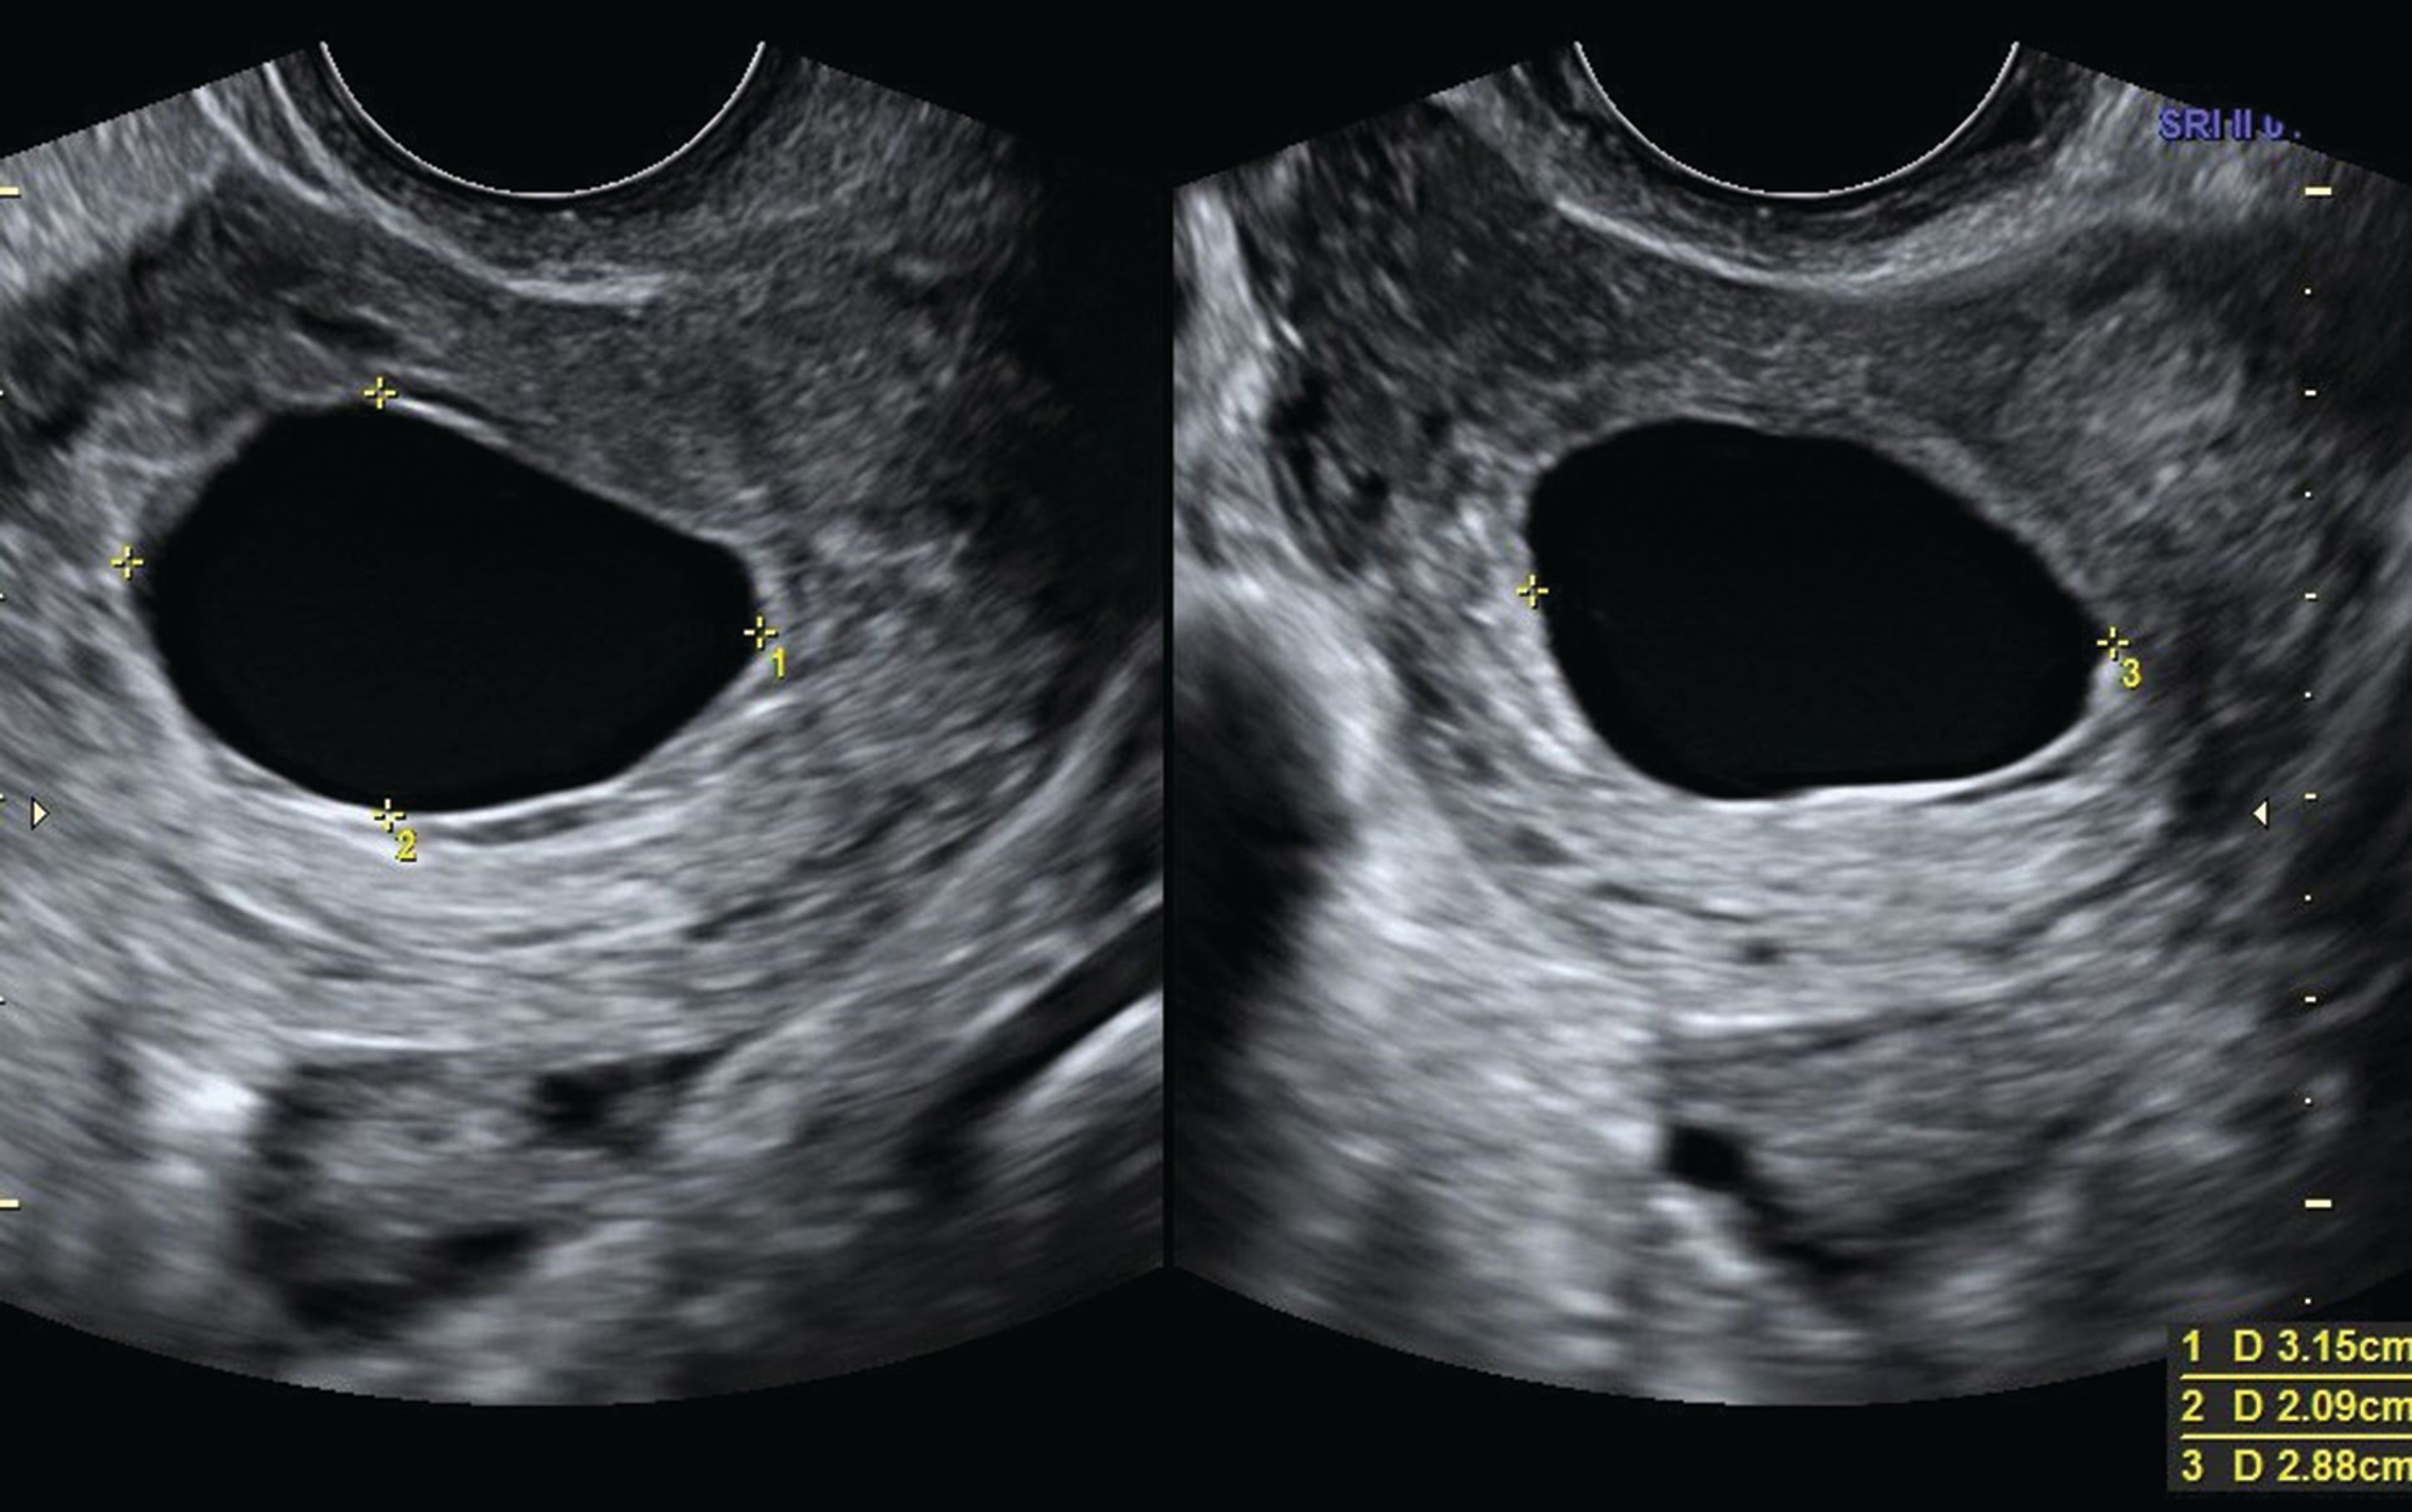

Like most expectant parents they couldnt wait to see the first glimpse of their little one. Ultrasound diagnosis of miscarriage should only be considered when either a mean gestation sac diameter is 25 mm with no obvious yolk sac or a fetal pole with a crown rump length of 7 mm without evidence of fetal cardiac activity. Im so sorry and really hope its a mistake and that youre still pregnant but there is a high chance of miscarriage in very early pregnancy such as yours.

But one look at the screen told Emily something wasnt right. Alicia Gatz who has been a sonographer for the past. Transvaginal ultrasound is the mainstay in the diagnosis of miscarriage.

Ultrasound Is A Critical Tool Of Managing Miscarriage